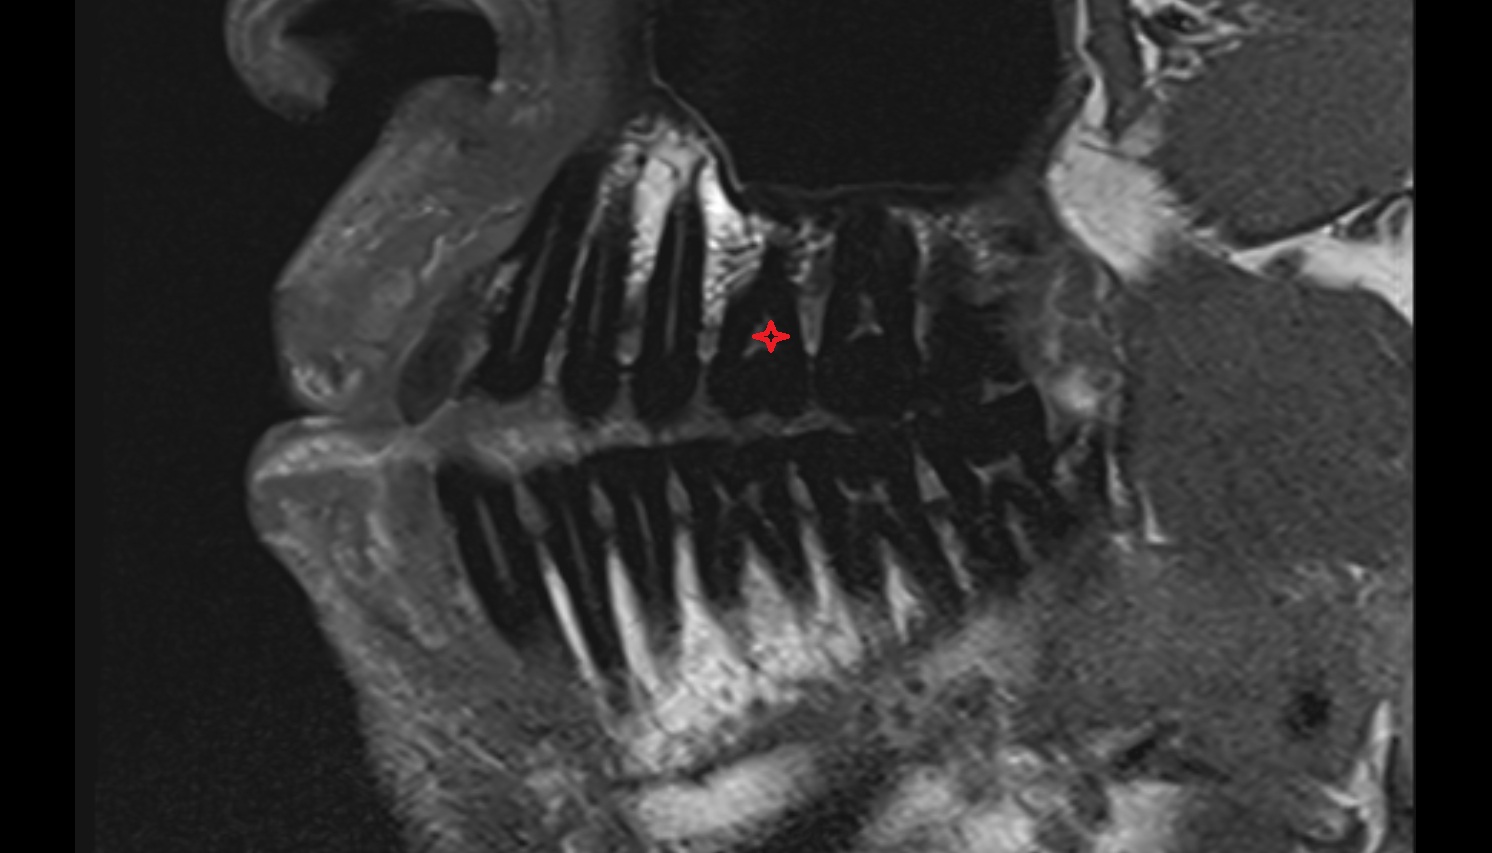

- Root of lower molar tooth

- Lower molar apical foramen

- Upper premolar apical foramen

- Root of upper molar tooth

- Root canal of upper molar tooth

- Dental pulp of upper molar tooth

- Dental pulp of upper premolar tooth

- Enamel of lower molar tooth

- Root canal of upper premolar tooth

- Enamel of upper molar tooth

- Enamel of upper incisor tooth

- Enamel of lower incisor tooth

- Enamel of lower premolar tooth

- Dental pulp of lower molar tooth

- Root canal of lower premolar tooth

- Lower premolar apical foramen

- Dental branches of inferior alveolar artery, vein, & nerve

- Alveolar process of maxilla